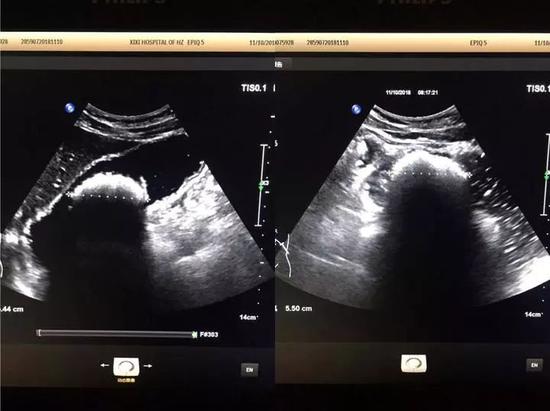

第三天,腹痛越加明顯,小張如約趕到市西溪醫(yī)院超聲科,潘林醫(yī)生給他仔細(xì)做了檢查,肝臟、膽囊等臟器一個(gè)個(gè)查過(guò)來(lái)都沒(méi)什么問(wèn)題,一直查到腹部時(shí),發(fā)現(xiàn)了一個(gè)“大家伙”,再放大鏡頭看,竟是胃里有個(gè)直徑5.5cm的結(jié)石。

5.5cm是什么概念?成人握拳后拳頭最長(zhǎng)的徑線一般為6—8cm,也就是說(shuō)小張胃里有差不多拳頭大小的石頭撐在那里,所以總是肚子疼。

亮亮的一團(tuán)就是胃結(jié)石 亮亮的一團(tuán)就是胃結(jié)石

在消化科醫(yī)生的指導(dǎo)下,小張很快開(kāi)始“可樂(lè)療法”。吃完早飯后先吃一顆保護(hù)胃粘膜的藥,休息個(gè)半小時(shí)后,喝一瓶500毫升的可樂(lè),接著中午正常飲食,到下午茶時(shí)間再喝一瓶500毫升的可樂(lè),晚上依然是正常吃飯。就這樣,什么罪都沒(méi)遭,什么事也沒(méi)耽誤,每天只是比平時(shí)多喝了兩瓶可樂(lè),申請(qǐng)的變化正在小張肚子里慢慢發(fā)生。三天后,他的腹痛癥狀緩解了;六天后,再?gòu)?fù)查B超,胃里的“大家伙”竟已不見(jiàn)蹤影。